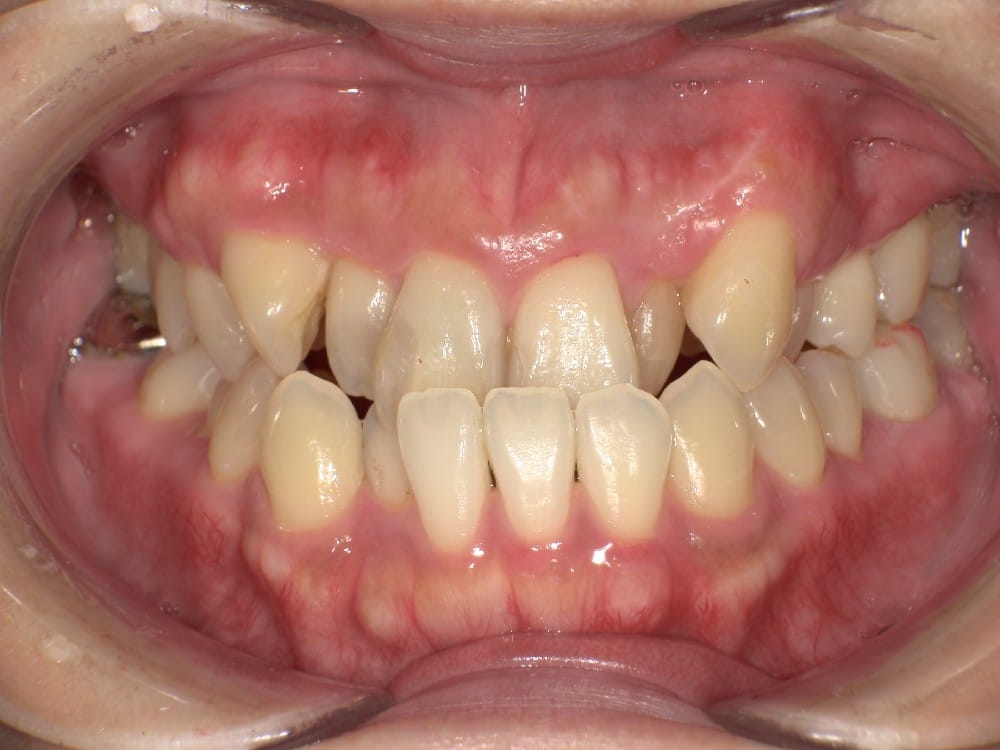

30代の男性で、受け口とガタガタを主訴にご来院されました。

治療前の様子

分析しますと

- 骨格的な上下あごの前後差は重度

- 噛み合わせの位置も下あごの奥歯が半分くらい前にズレていた

- 上の前歯が前に傾斜、下の前歯が内側に傾斜しているにもかかわらず、受け口

というケースで、外科的な処置も検討するようなケースでした。

骨格的なズレや奥歯の噛み合わせのズレもあり、重度の受け口でしたが、なんとか歯列矯正のみで受け口を改善できると診断し、治療を開始しました。

先ほどの2ケースと同じように、患者さまに外科的な手術の選択肢も提示しましたが、希望されず、横顔の変化はおそらく起こらないことを納得の上、治療をスタートいたしました。

今回のケースも奥歯の移動量が大きいため、マウスピースだけでは難しいと判断し、カリエールとよばれる装置を補助的に使用し、上下の噛み合わせの前後関係を整えることで、手術を行わずに機能面と見た目の両方が改善することにしました。

治療後の写真です。

<治療前後の比較です>

正面から見た時の受け口は改善していますが、横顔の変化は軽微かほとんど起こっていません。

同じように治したケースでも横顔の変化には差があります。

だからこそ、治療前に「どこまでを目標にするのか」をしっかり共有し、噛み合わせ改善を軸に治療を進めることが大切になります。